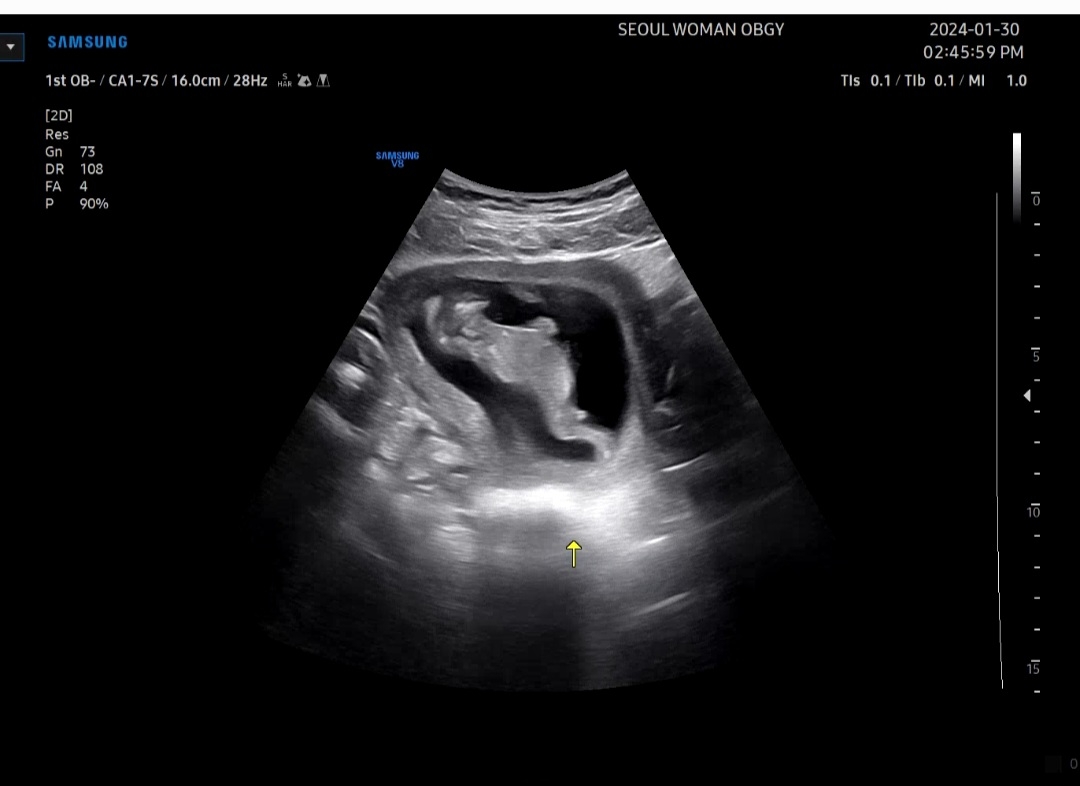

12주차때는 다 저렇게 나와있어서 성별은 모르겠지만 귀엽네용ㅋㅋㅋ

12주 1일차에 보러갔는데 펄쩍펄쩍 뛰더라구요 그땐 너무 귀여워서 행동만 봤는데 집에 와서 영상보니 배 아래에 !! 남자아이 일까요? 안보이다 보이다 그래용